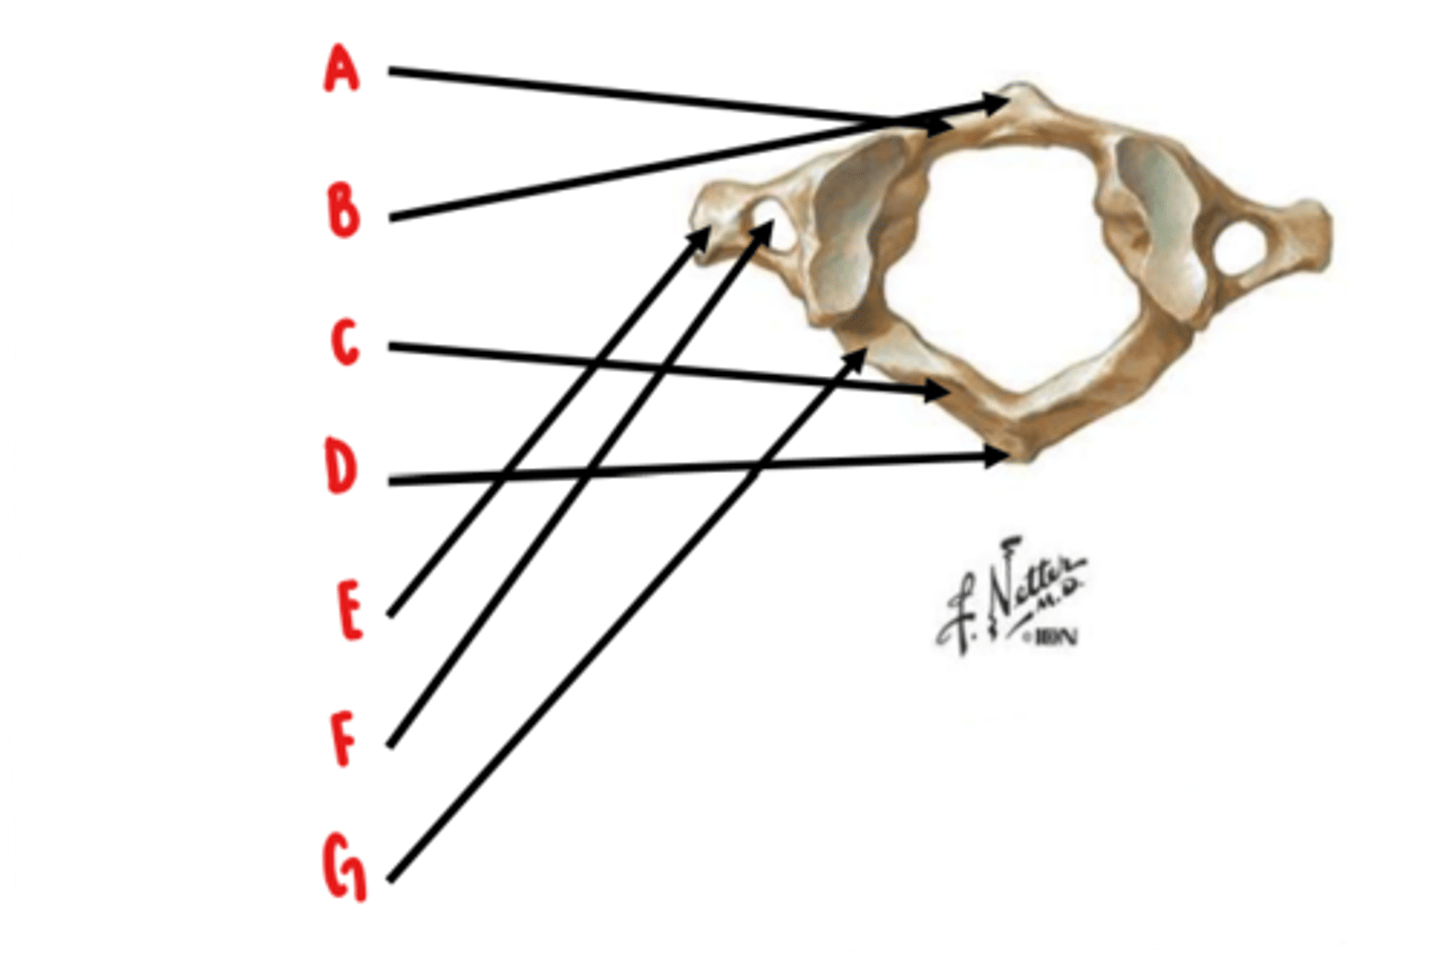

Atlas (C1)

What vertebrae is this?

anterior arch

Identify A

anterior tubercle

Identify B

posterior arch

Identify C

posterior tubercle

Identify D

transverse process

Identify E

transverse foramen

Identify F

groove for vertebral artery

Identify G